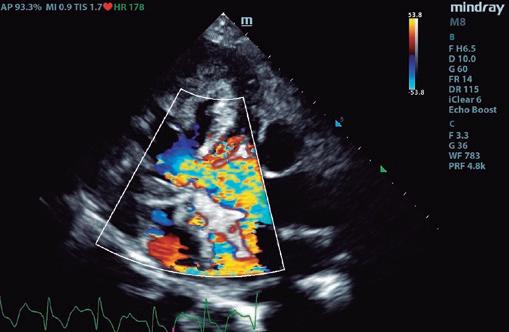

Boehringer Ingelheim España ha programado hasta final de año las Jornadas de Ecografía Avanzada patrocinadas por Vetmedin que recorrerán diversas ciudades del territorio nacional junto al referente Germán Santamarina. La finalidad de la iniciativa es brindar formación especializada y participativa a los especialistas en ecografía ambulante, un colectivo con necesidades muy específicas al cual Boehringer Ingelheim brinda su apoyo.

Las jornadas comenzaron en Barcelona y Alicante los días 21 y 22 de junio, respectivamente. Madrid, País Vasco y Andalucía y Canarias serán las siguientes durante las semanas del 23 de octubre y del 13 de noviembre. Todas las sesiones tienen una duración de medio día y se desarrollan en formato de mesa redonda a partir de las 15:00 h.

Con el objetivo de promover una experiencia más cercana e interactiva, las sesiones se organizan en grupos pequeños, con un límite de 10 a 15 participantes por sesión.